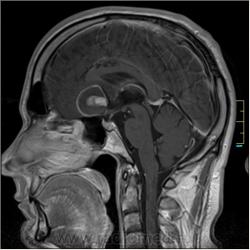

Пациентка направлена на исследование с диагнозом "Гипертонический криз"

Пациентка направлена на исследование с диагнозом "Гипертонический криз", энцефалопатия неуточненная.

частично функционирующая аневризма

Иначе говоря, аневризма с хронической геморрагией, т.к. мы видим фракции крови различного возраста.

По-моему, аневризма с пристеночными тромбами.

Постепенное пристеночное образование тромбов приводит к появлению типичного для аневризмы феномена -слоистости МР сигнала в полости аневризмы. Данная картина демонстрирует слоистый характер тромботических масс в полости аневризмы .Функционрирующая часть имеет низкий сигнал во всех режимах сканирования. Дополнительно-перифокальный отек.

А может более корректно интерпретировать как частично тромбированная аневризма... Уж коь речь идет о фракциях, ну то есть о тромбе по сути.... Ну и плюс перфокальный отек головного мозга (вероятнее цитотоксический+вазогенный).